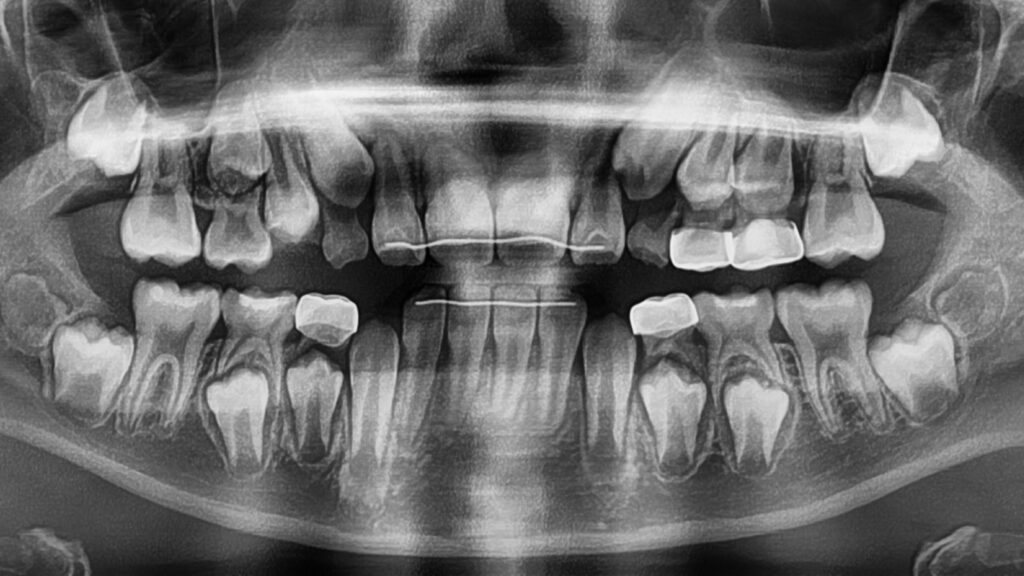

또한 1차 교정이 완료되었다고 해서 교정치료가 완전히 끝나는 것은 아닙니다.

모든 영구치 맹출이 완료된 후 2차 교정 필요성을 재평가하게 됩니다.(엑스레이로 확인)

이후 모든 영구치가 맹출하면서 추가적인 치아 배열이 필요한지 다시 한번 정밀하게 평가하여, 필요한 경우 2차 교정을 진행하게 됩니다.